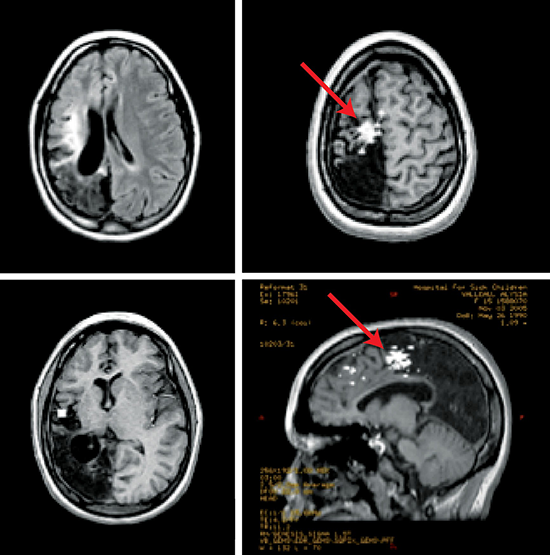

Imaging surgical epilepsy in children( 儿童癫痫手术 影像) 英文原文摘要: Abstract Introduction Epilepsy surgery rests heavily upon magnetic resonance imaging (MRI). Technical develop...

局灶性MRI异常增加了术前拟手术 治疗癫痫患者 的致痫区成功勾画的机会(Duncan和Sagar, 1987;Fish等人,1993年;斯宾塞,1995;艾蒙等,1996;Cascino, 2004;Tonini等人,20...

脑海绵状血管瘤和癫痫发作:病灶切除术还是癫痫手术?海绵状血管瘤(CMs)是一种越来越被公认的部分性癫痫的原因。这些良性的桑葚样血管病变可能发生...